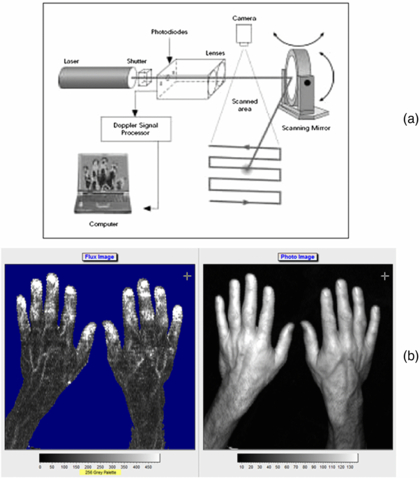

Standard image High-resolution imageThe technique depends on the Doppler principle whereby low power light from a monochromatic stable laser e.g. a 633 nm helium neon gas laser or a single mode 670 or 780 nm laser diode, incident on tissue is scattered by moving red blood cells and as a consequence is frequency-broadened. The frequency-broadened light, together with laser light scattered from static tissue, is photo-detected, and the resulting photocurrent is processed. The high spatial variability in blood flow across tissue such as the skin limits the clinical utility of single point LDF measurements. However, this limitation can be overcome with LDPI which provides a two-dimensional colour-coded representation of blood flow for the imaged tissue (figure 2(a)). Furthermore a key advantage of LDPI is that it is non-contact and the target tissue size can be configured to optimize the spatial resolution. Typical square field sizes range from a few centimetres up to 0.5 m (figure 2(b)).

Figure 2. (a) Schematic diagram of raster scanning based LDPI technology. (b) Example of LDPI of the hands alongside a visible light image. The increased perfusion is easily seen through the finger nails and on the edge of the thumb. The perfusion scale is also shown. (Courtesy of Moor Instruments.)